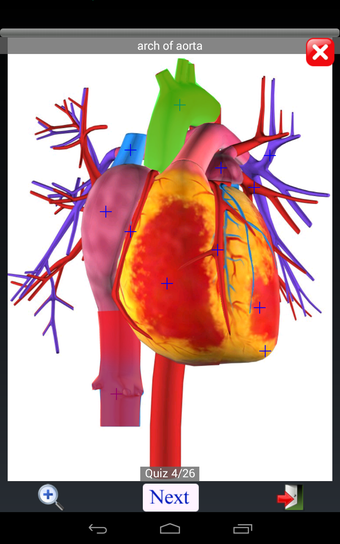

Anatomy Quiz Free es una aplicación de Android de Education Mobile que ofrece una amplia gama de cuestionarios para ayudar a los usuarios a aprender anatomía humana. La aplicación cuenta con más de 500 cuestionarios que ponen a prueba tu capacidad para identificar la ubicación correcta de un objeto dado su nombre. Los cuestionarios se generan a partir de modelos de anatomía 3D virtuales, lo que los hace más atractivos e interactivos. La aplicación es gratuita y no hay versiones premium ni compras dentro de la aplicación.

La aplicación es compatible con los idiomas inglés, francés, español y alemán, lo que la hace accesible para usuarios de diferentes partes del mundo. Las imágenes de alta resolución son nítidas y claras, y la función de zoom con pellizco te permite acercar y alejar las imágenes para una mejor vista. El cuestionario de posición viene con un temporizador, lo que lo hace más desafiante y emocionante. Además, la aplicación tiene una función de transferencia a la tarjeta SD, lo que facilita su transferencia a otros dispositivos.